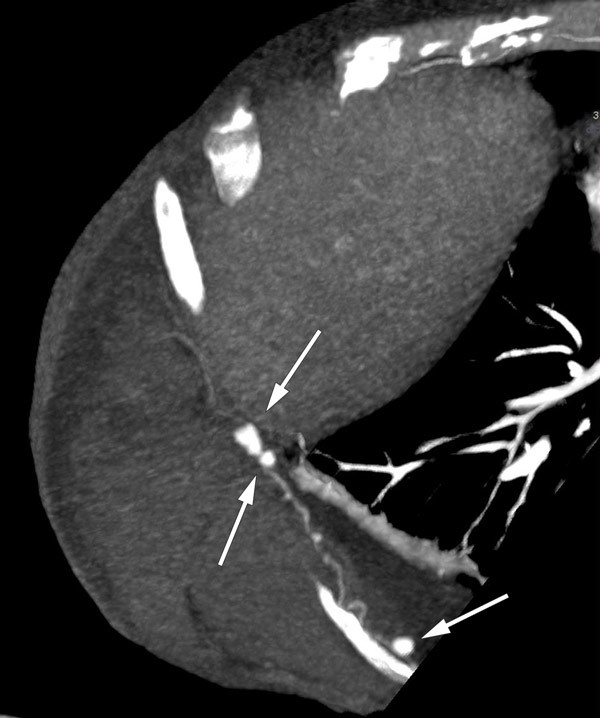

I rekonvalesensperioden etter den andre tarmoperasjonen fikk kvinnen på nytt en stor blødning, denne gang fra den høyre nyren. På CT-arteriografi fant man blødning subkapsulært, inferiort mot høyre fossa iliaca og høyre flanke. Hun ble tilsett av urolog, som konkluderte med konservativ behandling i form av blodtransfusjon.

Som regel blir diagnosen stilt ut fra biopsi med funn av transmural nekrotiserende inflammasjon i mellomstore arterier. Alternativet til biopsi er typiske angiografifunn av multiple aneurismer og stenoser. CT- og MR-undersøkelse har i stor grad erstattet konvensjonell angiografi, og CT thorax/abdomen av vår pasient viste multiple karaneurismer og pseudoaneurismer i tarmkrøs, rundt ventrikkel, i lever, nyrer og interkostalarterier. Hun fikk standard behandling for tilstanden med steroider og cyklofosfamid,